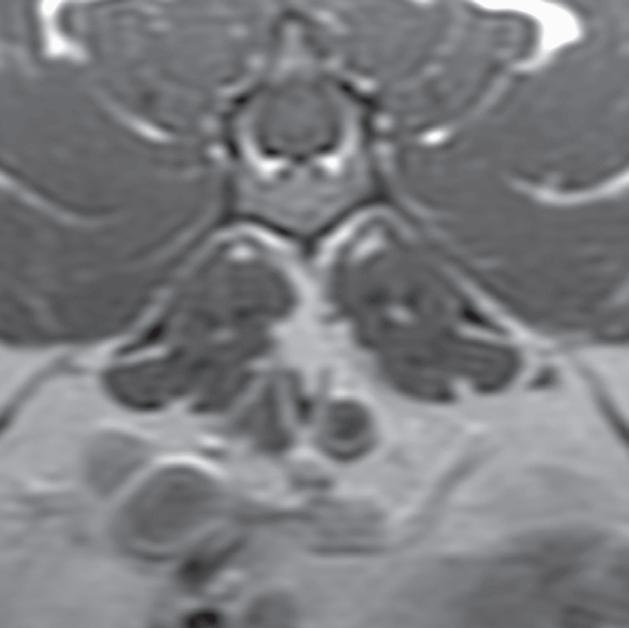

Rycina 5.6.6. Przysadkowozależna nadczynność kory nadnerczy (pies) TK

Badanie wykonano u 12-letniego, kastrowanego boston teriera z podejrzeniem przysadkowozależnej nadczynności kory nadnerczy. W badaniu natywnym oba nadnercza (a, b – strzałki) są powiększone i zaokrąglone, a także wykazują jednorodną densyjność tkanek miękkich. Widoczna jest mineralizacja ściany tętnicy krezkowej przedniej, która jest zmianą wtórną do zespołu Cushinga (b – gwiazdka). Obraz po podaniu dożylnego środka kontrastowego mózgowia ujawnia duży, intensywnie wzmacniający się rozrost przysadki (d – otwarta strzałka), przypuszczalnie o charakterze funkcjonalnym